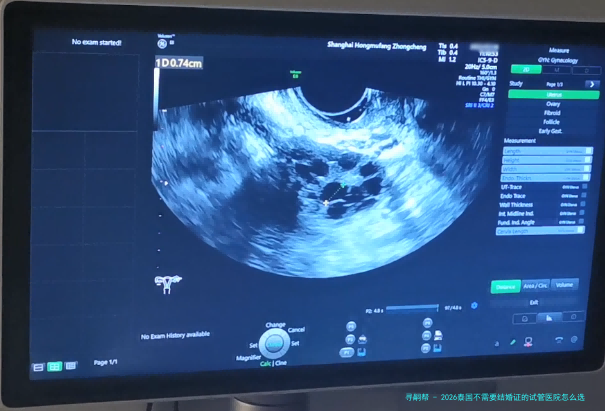

4.促排卵取精:在超声疏通下将成熟的卵子拿出,同时采集男方的精子。

4.促排卵取精:在超声疏通下将成熟的卵子拿出,同时采集男方的精子。

4.促排卵取精:在超声疏通下将成熟的卵子拿出,同时采集男方的精子。

4.促排卵取精:在超声疏通下将成熟的卵子拿出,同时采集男方的精子。

4.促排卵取精:在超声疏通下将成熟的卵子拿出,同时采集男方的精子。